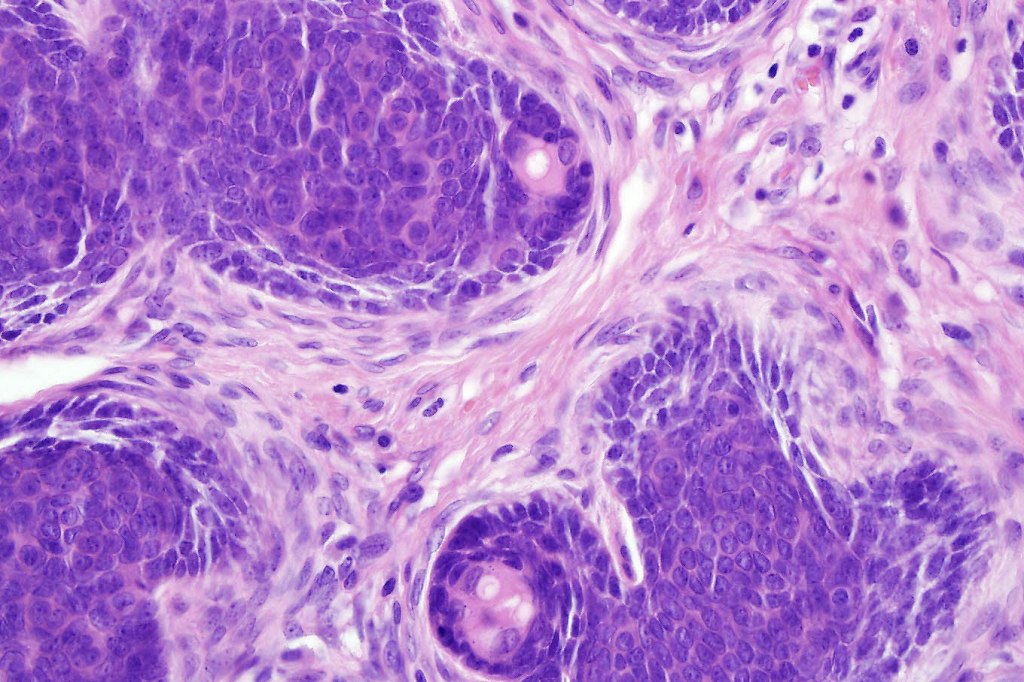

•Variably sized but generally large, basophilic tumor nodules composed of small uniform basaloid cells with minimal cytoplasm

•Peripheral palisading but no retraction artifact or stromal mucin deposition

•A rich fibromyxoid mesenchymal stroma with variable papillary mesenchymal bodies (sometimes these are absent)

•Trichogerminoma is a distinctive variant being composed of tumor nodules with basaloid cells surrounding pale or eosinophilic micronodules (Zellballen)